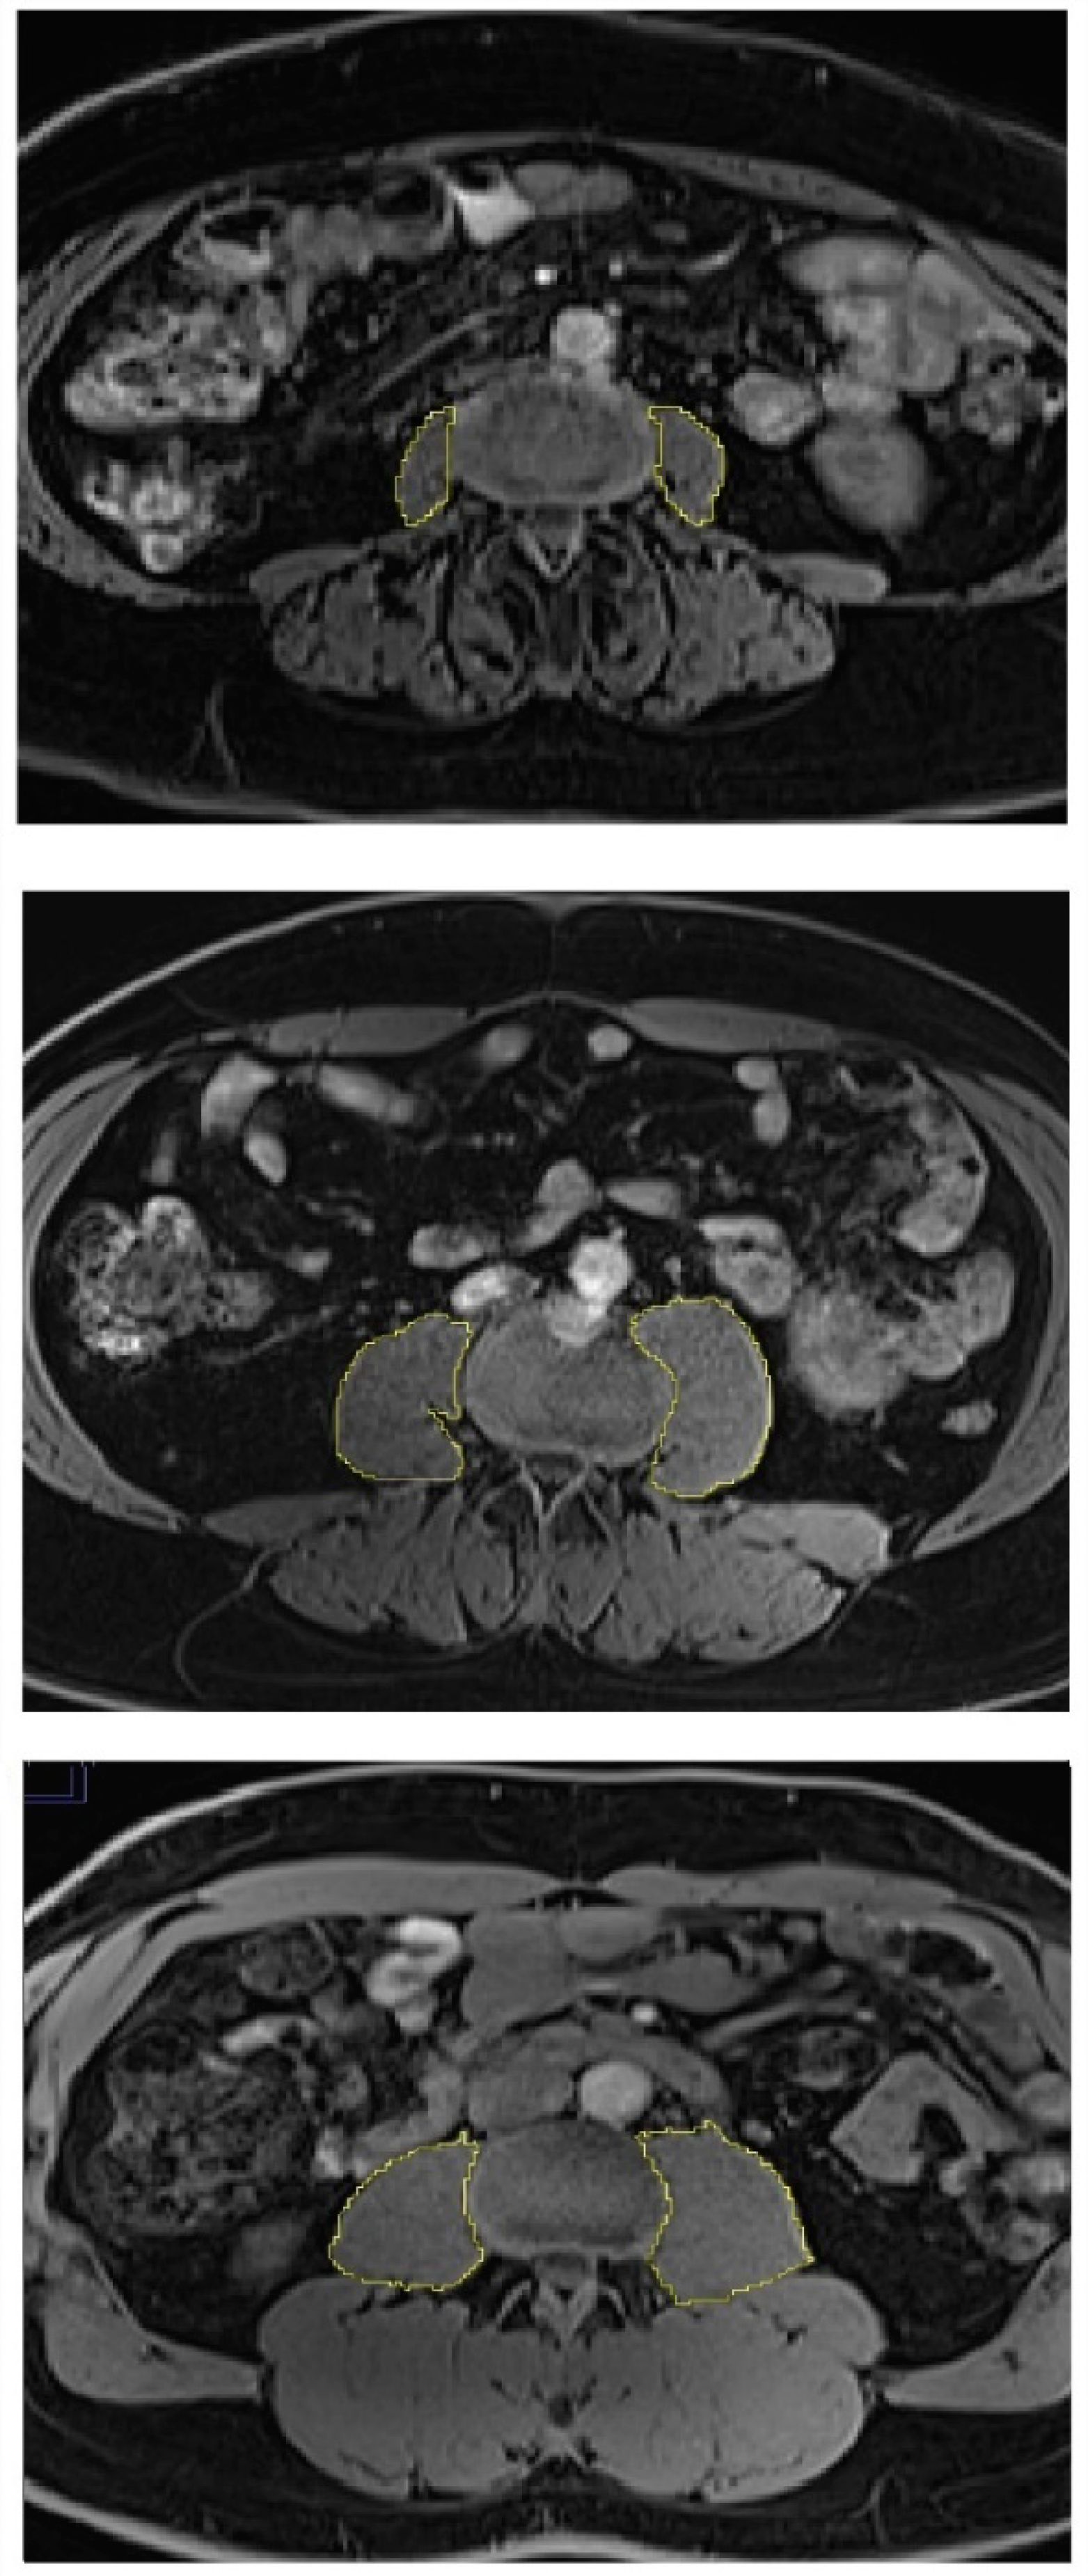

Abdominal MR scans were performed in all participants using 3.0 Tesla MAGNETOM Skyra® MR scanner (Siemens, Erlangen, Germany). Details of the protocol were described elsewhere [21]. PMV was calculated in cm3 by measuring the cross-sectional area of the left and right psoas major muscle from the second lumbar vertebral level to the fifth lumbar vertebral level and multiplying it by the thickness of MR slices (0.3 cm), as described in detail elsewhere [22]. Representative measurements of PMV are displayed in Figure 1. SMFD was determined from the cross-sectional area (in pixels) of the left and right paraspinous muscles (i.e., iliocostalis, longissimus, and multifidus) at the lower endplate of the third lumbar vertebra (total paraspinous area), as described in detail elsewhere [23]. Representative measurements of SMFD are displayed in Figure 2.

Figure 1.

Skeletal muscle size in individuals with diabetes (upper panel), prediabetes (middle panel), and normoglycemia (lower panel). Psoas muscle was used for skeletal muscle size measurements.